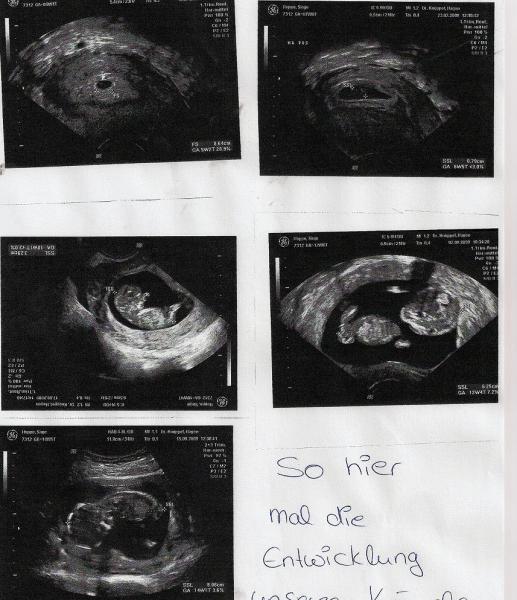

Und hier mal alle USBilder die ich schon bekommen habe. DIe ersten 4 sind per Vaginalus und das letzte über den Bauch geschallt worden LG Sinje

ich find das auf der 2 reihe das 2 toll ... da siehe sie so alienartig aus :D

ja das find ich auch wie nen kleiner alien ... mal sehen nächste woche freitag muss ich wieder hin .) hoffentlich sehen wir dann was es wird.. dann bin ich 18.ssw. und letzten male konnte er nix sagen vll is das ja nen zeichen auf ein mädchen??? bei collin haben wir es schon in der 12.ssw gewusst